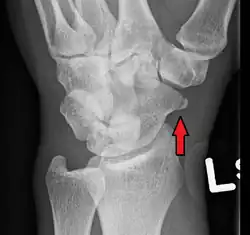

| An X-ray showing a fracture through the waist of the scaphoid | |

Scaphoid fractures are often diagnosed by PA and lateral X-rays. However, not all fractures are apparent initially.[7] Therefore, people with tenderness over the scaphoid (those who exhibit pain to pressure in the anatomic snuff box ) are often splinted in a thumb spica for 7–10 days at which point a second set of X-rays is taken.[7] If there was a hairline fracture, healing will now be apparent. Even then a fracture may not be apparent. A CT Scan can then be used to evaluate the scaphoid with greater resolution. The use of MRI, if available, is preferred over CT and can give one an immediate diagnosis.[9] Bone scintigraphy is also an effective method for diagnosis fracture which do not appear on Xray.[10]

A subtle scaphoid fracture -

A more obvious scaphoid fracture on a scaphoid view X ray -